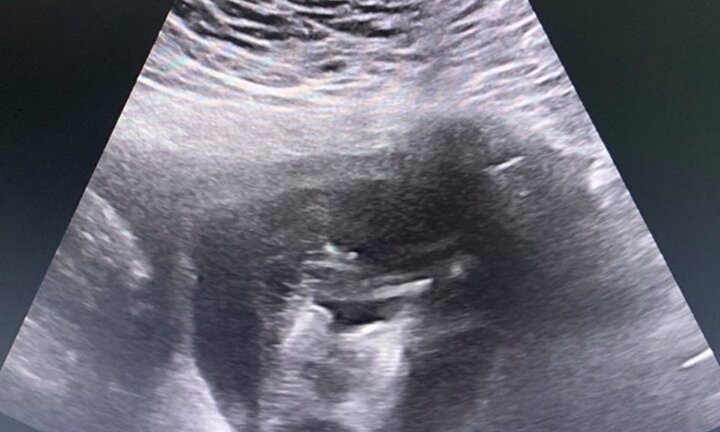

Một cô gái trẻ ở Tuyên Quang mang song thai dính nhau từ phần phần ngực xuống đến phần bụng, có chung một quả tim.